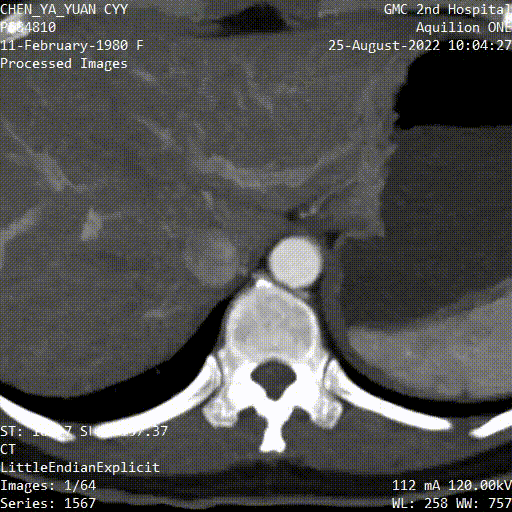

图为:入院CT及增强

图为:CT 三维重建

全腹CT及增强:下腔静脉滤器留置,无血栓

图为:入院全腹部CT及增强扫描